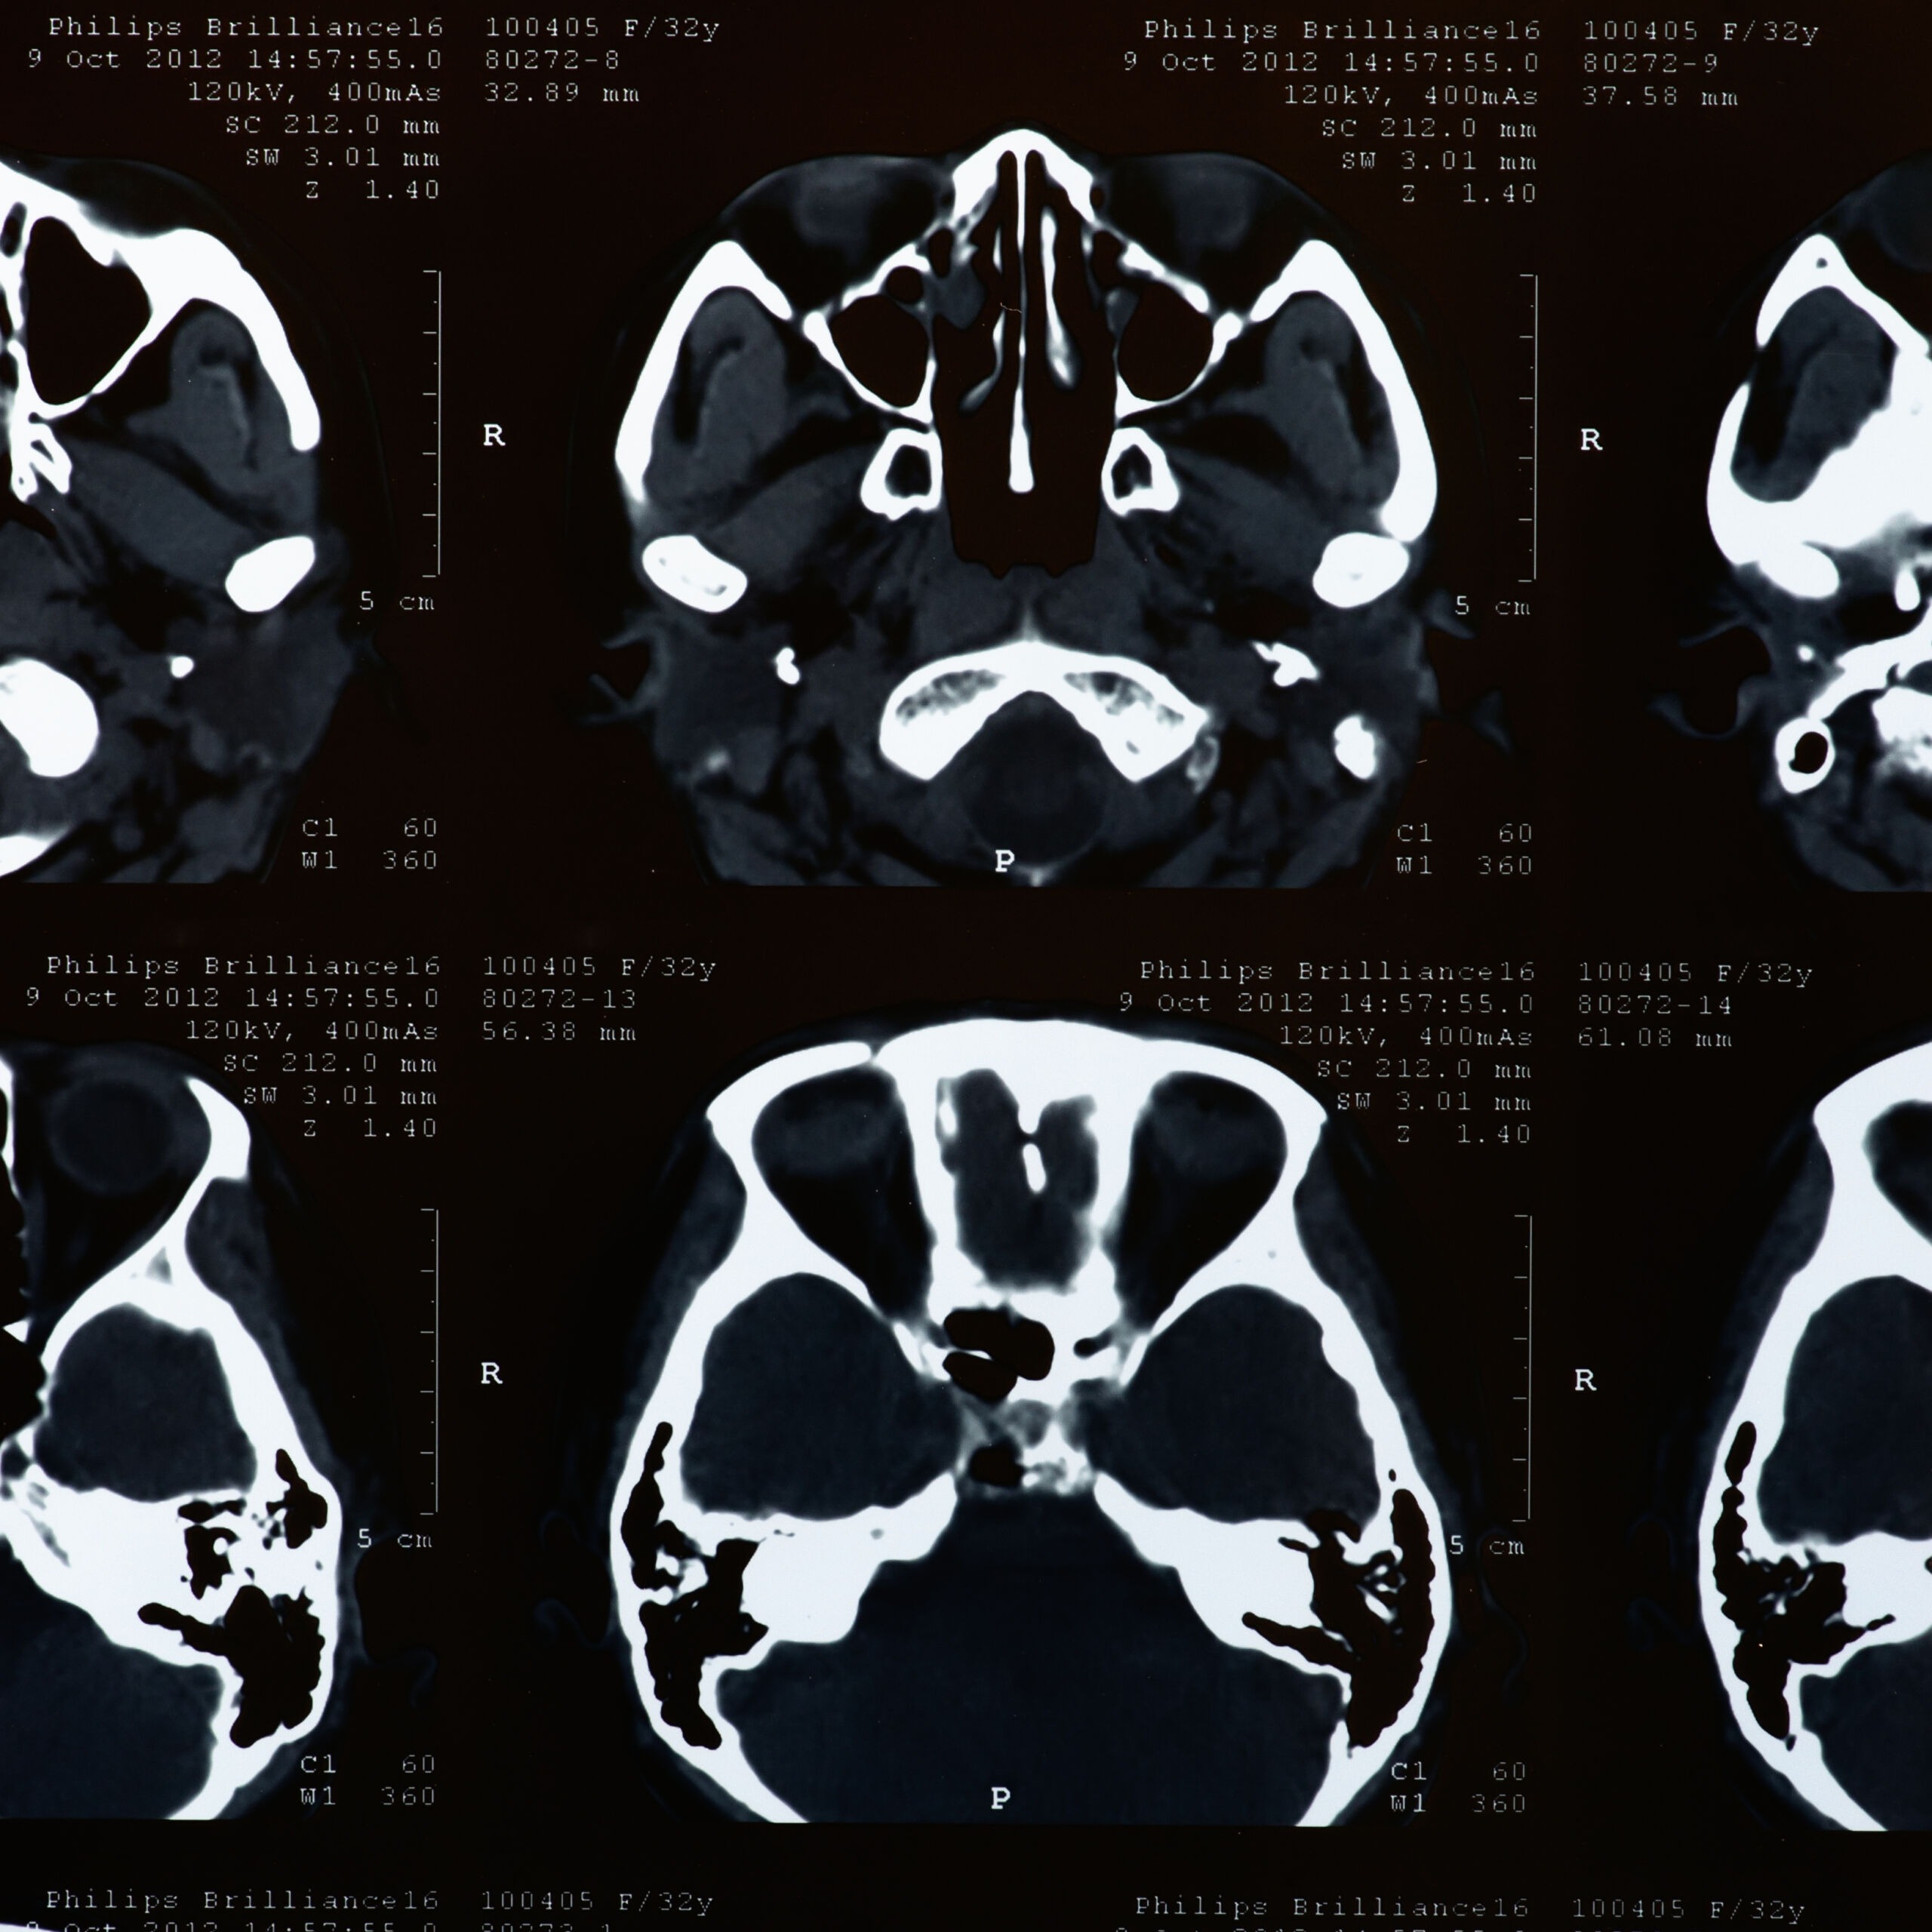

John, aged 44, first visited his GP complaining of a painful, red right eye with blurred vision, light sensitivity and a foreign body sensation that had started suddenly two days earlier. The GP noted conjunctival injection and a small corneal abrasion but prescribed antibiotic eye drops and advised follow-up if symptoms did not improve within 48 hours. No referral to ophthalmology was made at this stage.

Within 24 hours of the second GP visit John’s vision in the right eye had deteriorated to hand movements only. He attended A&E where an ophthalmologist finally examined him and diagnosed severe bacterial keratitis with corneal ulceration and hypopyon. Urgent treatment with intensive topical antibiotics, cycloplegics and admission was commenced, but the delay caused by medical negligence had already resulted in extensive corneal scarring and profound vision loss.